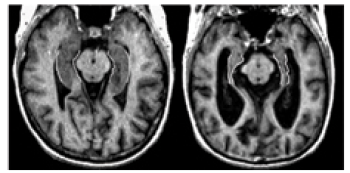

Lorsque les cellules du cerveau se détériorent et meurent, le cerveau se réduit fortement dans certaines zones.

Ce phénomène a tout d’abord été observé par le docteur Alzheimer lorsqu’il a étudié le cerveau d’Auguste Deter, la première personne à recevoir officiellement un diagnostic de maladie d’Alzheimer; on l’observe encore chez les personnes atteintes de la maladie d’Alzheimer aujourd’hui.

Les tissus cérébraux d’une personne en bonne santé (à gauche) sont plus élevés que ceux d’une personne atteinte de la maladie d’Alzheimer (à droite).

Images IRM; avec l’autorisation du Sunnybrook and Women’s College Health Sciences Centre.

Illustration : les tissus cérébraux d’une personne en bonne santé (à gauche) sont plus élevés que ceux d’une personne atteinte de la maladie d’Alzheimer (à droite).

Cette contraction continue à mesure de la progression de la maladie; elle affecte les fonctions du cerveau et aggrave les symptômes.